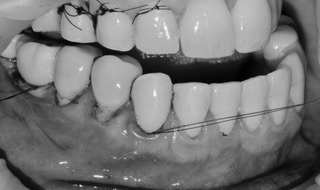

Revisión al año: